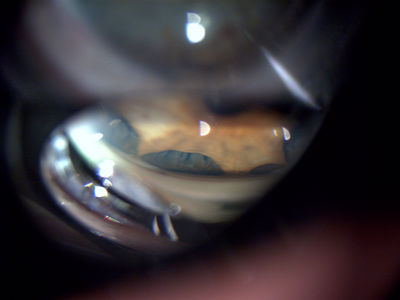

Trauma injury showing iris root detachment - Superior angle gonio view

Trauma injury showing iris root detachment. Injury from 20 years ago, has had phaco/IOL. Superior angle viewed with a Goldmann 3-mirror goniolens. Taken with a Topcon - DC1.